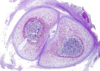

Osteochondrosis

Osteochondrosis latens - well-demarcated area of necrosis of cartilage

Osteochondrosis manifesta - arrows = associated with areas of foci of necrosis - areas of retained cartilage = hypertrophic chondrocytes

Osteochondrosis dissecans - arrow pointing to 'joint mice'